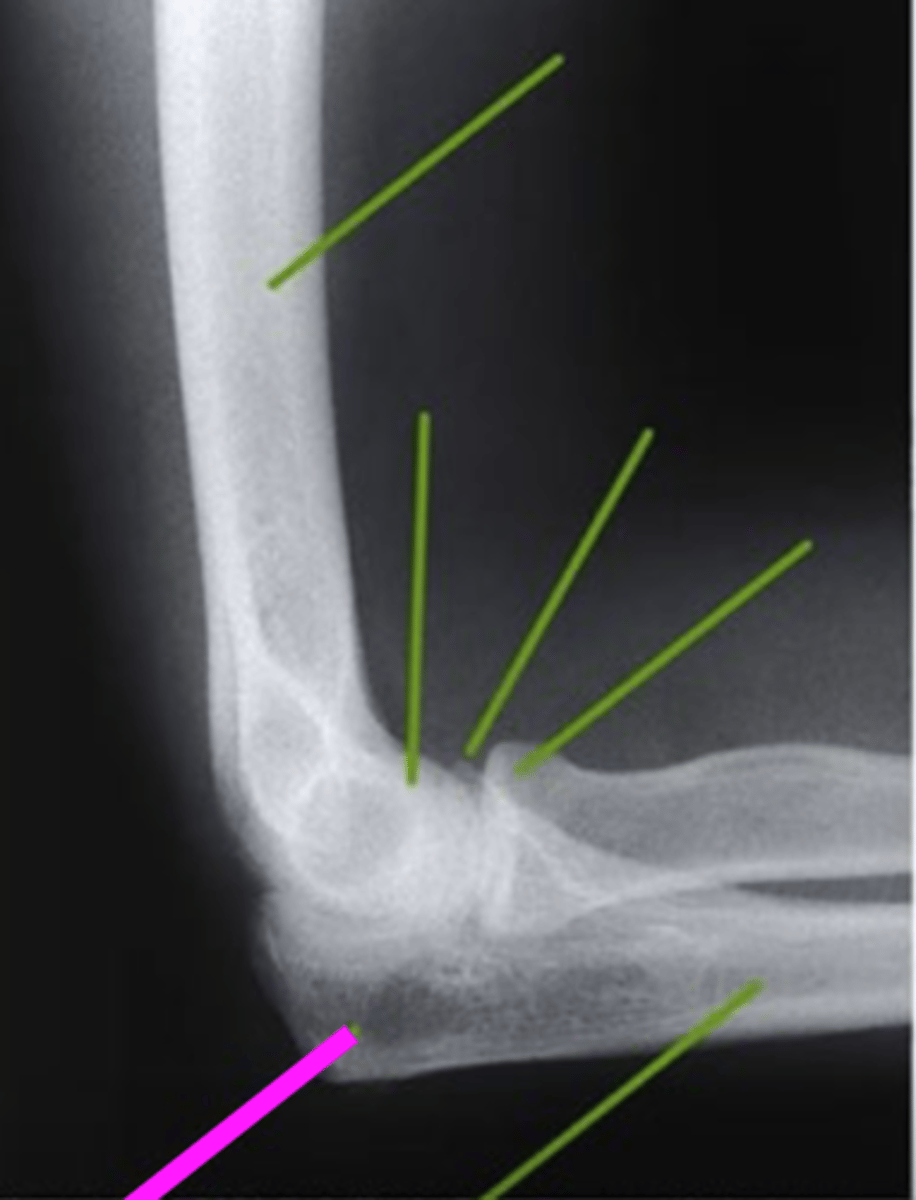

AP forearm

what view is this?

olecranon process

what does this pink line point to?

trochlea

capitulum

humeroradial joint

proximal radioulnar joint

radial tuberosity

radial styloid

distal radioulnar joint

scaphoid

lunate